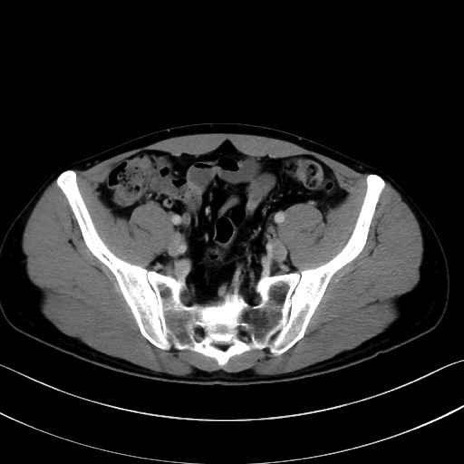

腸骨筋 (Iliacus)

肛門挙筋 (Levator ani)